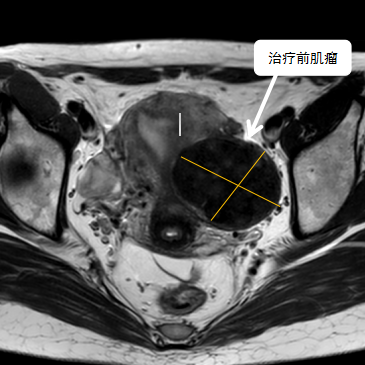

術(shù)前影像資料

經(jīng)過兩個(gè)月的藥物預(yù)處理,完善術(shù)前準(zhǔn)備,治療當(dāng)天陳主任帶領(lǐng)團(tuán)隊(duì)在3.0T磁共振清晰圖像引導(dǎo)下對(duì)子宮肌瘤進(jìn)行精準(zhǔn)消融,患者全程清醒,沒有明顯疼痛,經(jīng)過1個(gè)多小時(shí)的精細(xì)操作,手術(shù)非常成功,消融率接近90%,內(nèi)膜未見損傷!觀察一個(gè)小時(shí)后患者即自行回家。